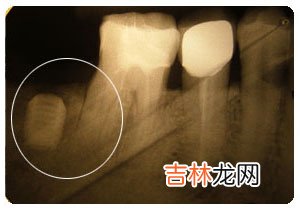

【做冠为什么要磨牙】 做各类冠都要磨除大量牙体组织,其目的是为了形成良好的固位型和抗力型 。一般磨牙时在能满足固位型与抗力型要求的情况下尽量减少牙体组织的破坏 。

牙体预备要求: